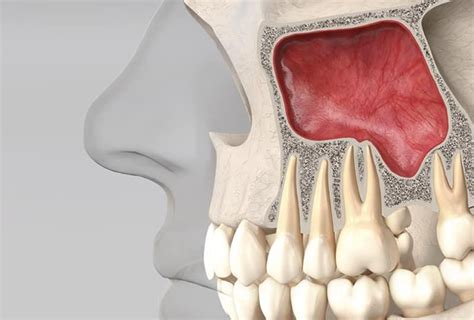

Elevación de Seno Maxilar

Con esta cirugía podemos aumentar el hueso de la arcada dentaria superior. En los pacientes que han experimentado pérdida ósea en la zona superior posterior, la elevación de seno maxilar es una técnica efectiva.

Este procedimiento implica levantar la membrana del seno maxilar y colocar un injerto óseo en el espacio creado, lo cual permite aumentar la altura del hueso en el área molar superior.

Los senos paranasales son unas cavidades llenas de aire ubicadas en los huesos del cráneo y la cara, concretamente en la zona que se encuentra alrededor de la nariz. Dentro de los senos paranasales podemos distinguir los senos maxilares, que son los más grandes y están ubicados debajo de los ojos, en el hueso maxilar. En función de la morfología y la anatomía que presente cada persona los senos maxilares pueden tener unas características diferentes.

Para llevar a cabo este procedimiento, el implantólogo debe levantar la membrana de Schneider -la cual recubre el hueso maxilar- y crear un espacio entre este y la membrana. El hueso artificial está basado en una sustancia denominada hidroxiapatita de calcio, la cual es biocompatible. Por lo general, tras este tratamiento, es necesario esperar alrededor de seis meses para realizar la cirugía de colocación de implantes dentales. Sin embargo, hay algunos casos en los que es posible colocar el implante inmediatamente después de la elevación de seno.

La elevación de seno maxilar tiene como propósito ganar altura de hueso al seno maxilar para facilitar la colocación de implantes dentales. Esto se logra mediante la aplicación de un injerto óseo en el espacio correspondiente.